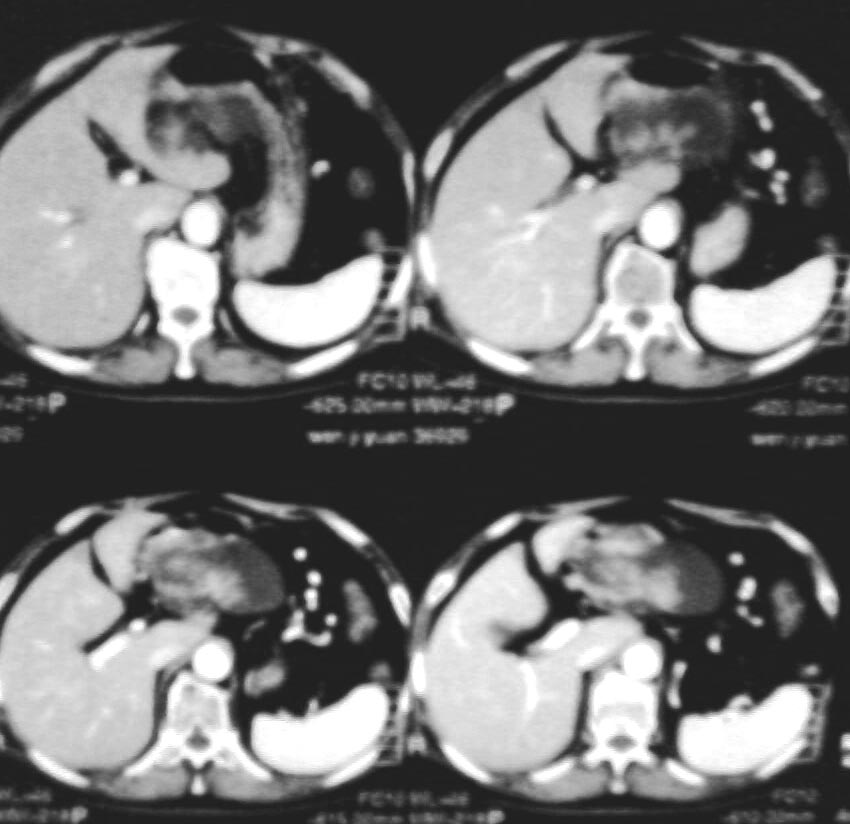

与中国医学影像网中“今日病例”(12-2)类似——胰管乳头状粘液瘤。

考虑胰腺黏液腺癌.低度恶性.

考虑胰管乳头状粘液瘤

1与中国医学影像网中“今日病例”(12-2)类似——胰管乳头状粘液瘤

2考虑胰腺黏液腺癌.低度恶性.

1.胰腺囊腺ca